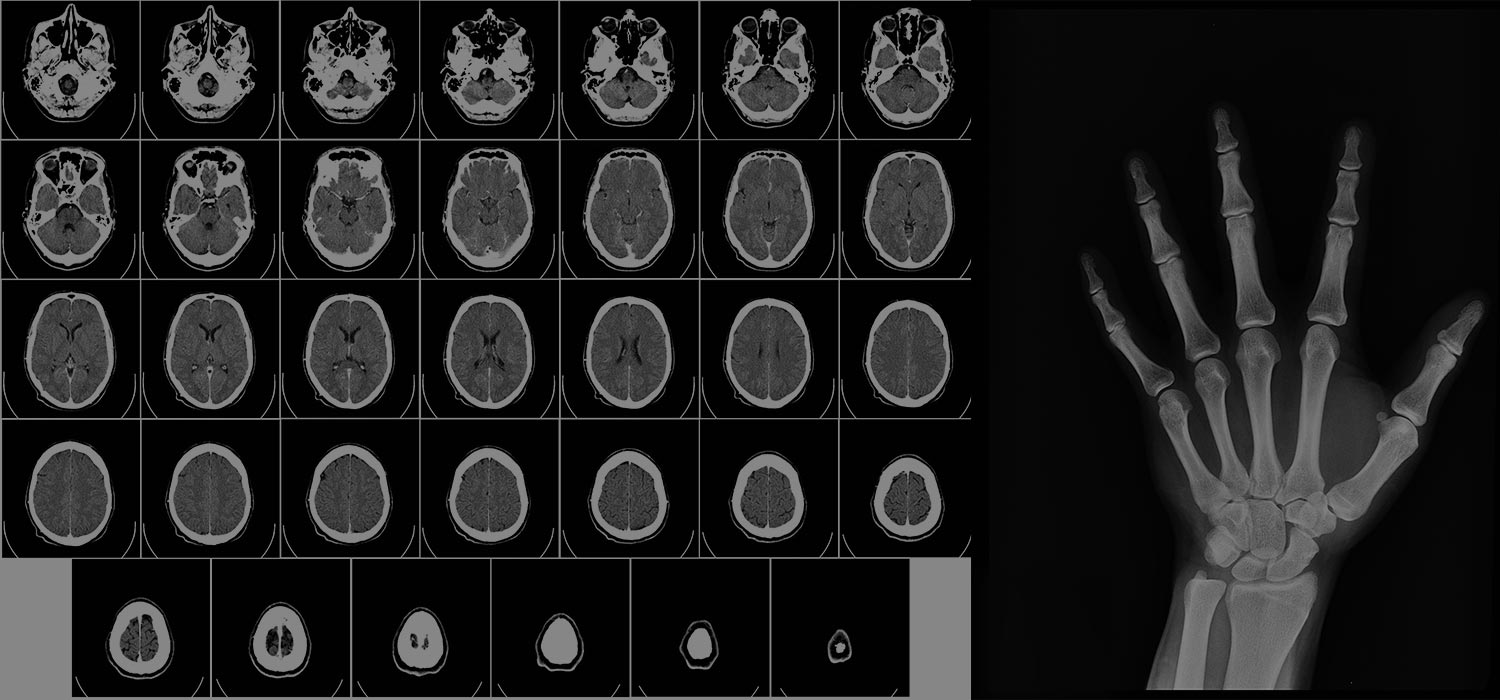

Medicine will play an increasingly important role. An important goal of PM is to stratify patients into different risk groups to make individualised decisions about prevention and treatment. To this end, there is great potential for using quantitative imaging biomarkers that can characterise perfusion, blood flow, metabolism, and cellularity. However, standardisation and quality assurance measures must be implemented before imaging biomarkers are widely adopted in clinical routine. Differences in imaging modalities and user experiences are important standardisation issues. Radiation genomics and nano theranostics are two emerging fields in which radiology plays an important role. Radiogenomics creates a link between diagnostic imaging and genomic function. A promising new field of nano theranostics is the use of drugs and contrast agents in a single entity, allowing real-time drug delivery and distribution monitoring.